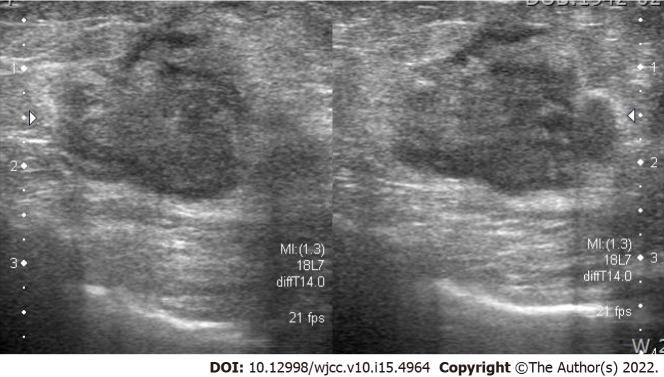

We report a case of MBC in a 78-year-old man. He visited our clinic with a palpable mass on the left breast with no masses in the axillary areas. He had previously undergone robot-assisted laparoscopic radical prostatectomy for prostate cancer, but there was no family history of malignancy. The breast mass was visible on ultrasonography, mammography, and magnetic resonance imaging, and chest computed tomography revealed a lung mass in the posterior basal segment of the right lower lobe. The patient was diagnosed with metaplastic carcinoma on core needle biopsy with lung metastasis. Total mastectomy with sentinel lymph node biopsy and video-assisted segmentectomy of the right lung was performed. However, multiple metastases appeared 3 mo after surgery in the brain, chest, and abdomen, and the patient died 5 mo after the initial diagnosis.

我们报告一例78岁男性的MBC病例。他因左侧乳房可触及肿块前来我院就诊,腋窝区域未触及肿块。他曾因前列腺癌接受机器人辅助腹腔镜根治性前列腺切除术,但无恶性肿瘤家族史。乳房肿块在超声、乳腺X线摄影和磁共振成像中均可见,胸部计算机断层扫描显示右下叶后基底段有一个肺部肿块。经粗针活检确诊为化生性癌伴肺转移。行全乳切除术加前哨淋巴结活检及右肺电视辅助节段切除术。然而,术后3个月脑、胸、腹出现多处转移,患者在初诊后5个月死亡。